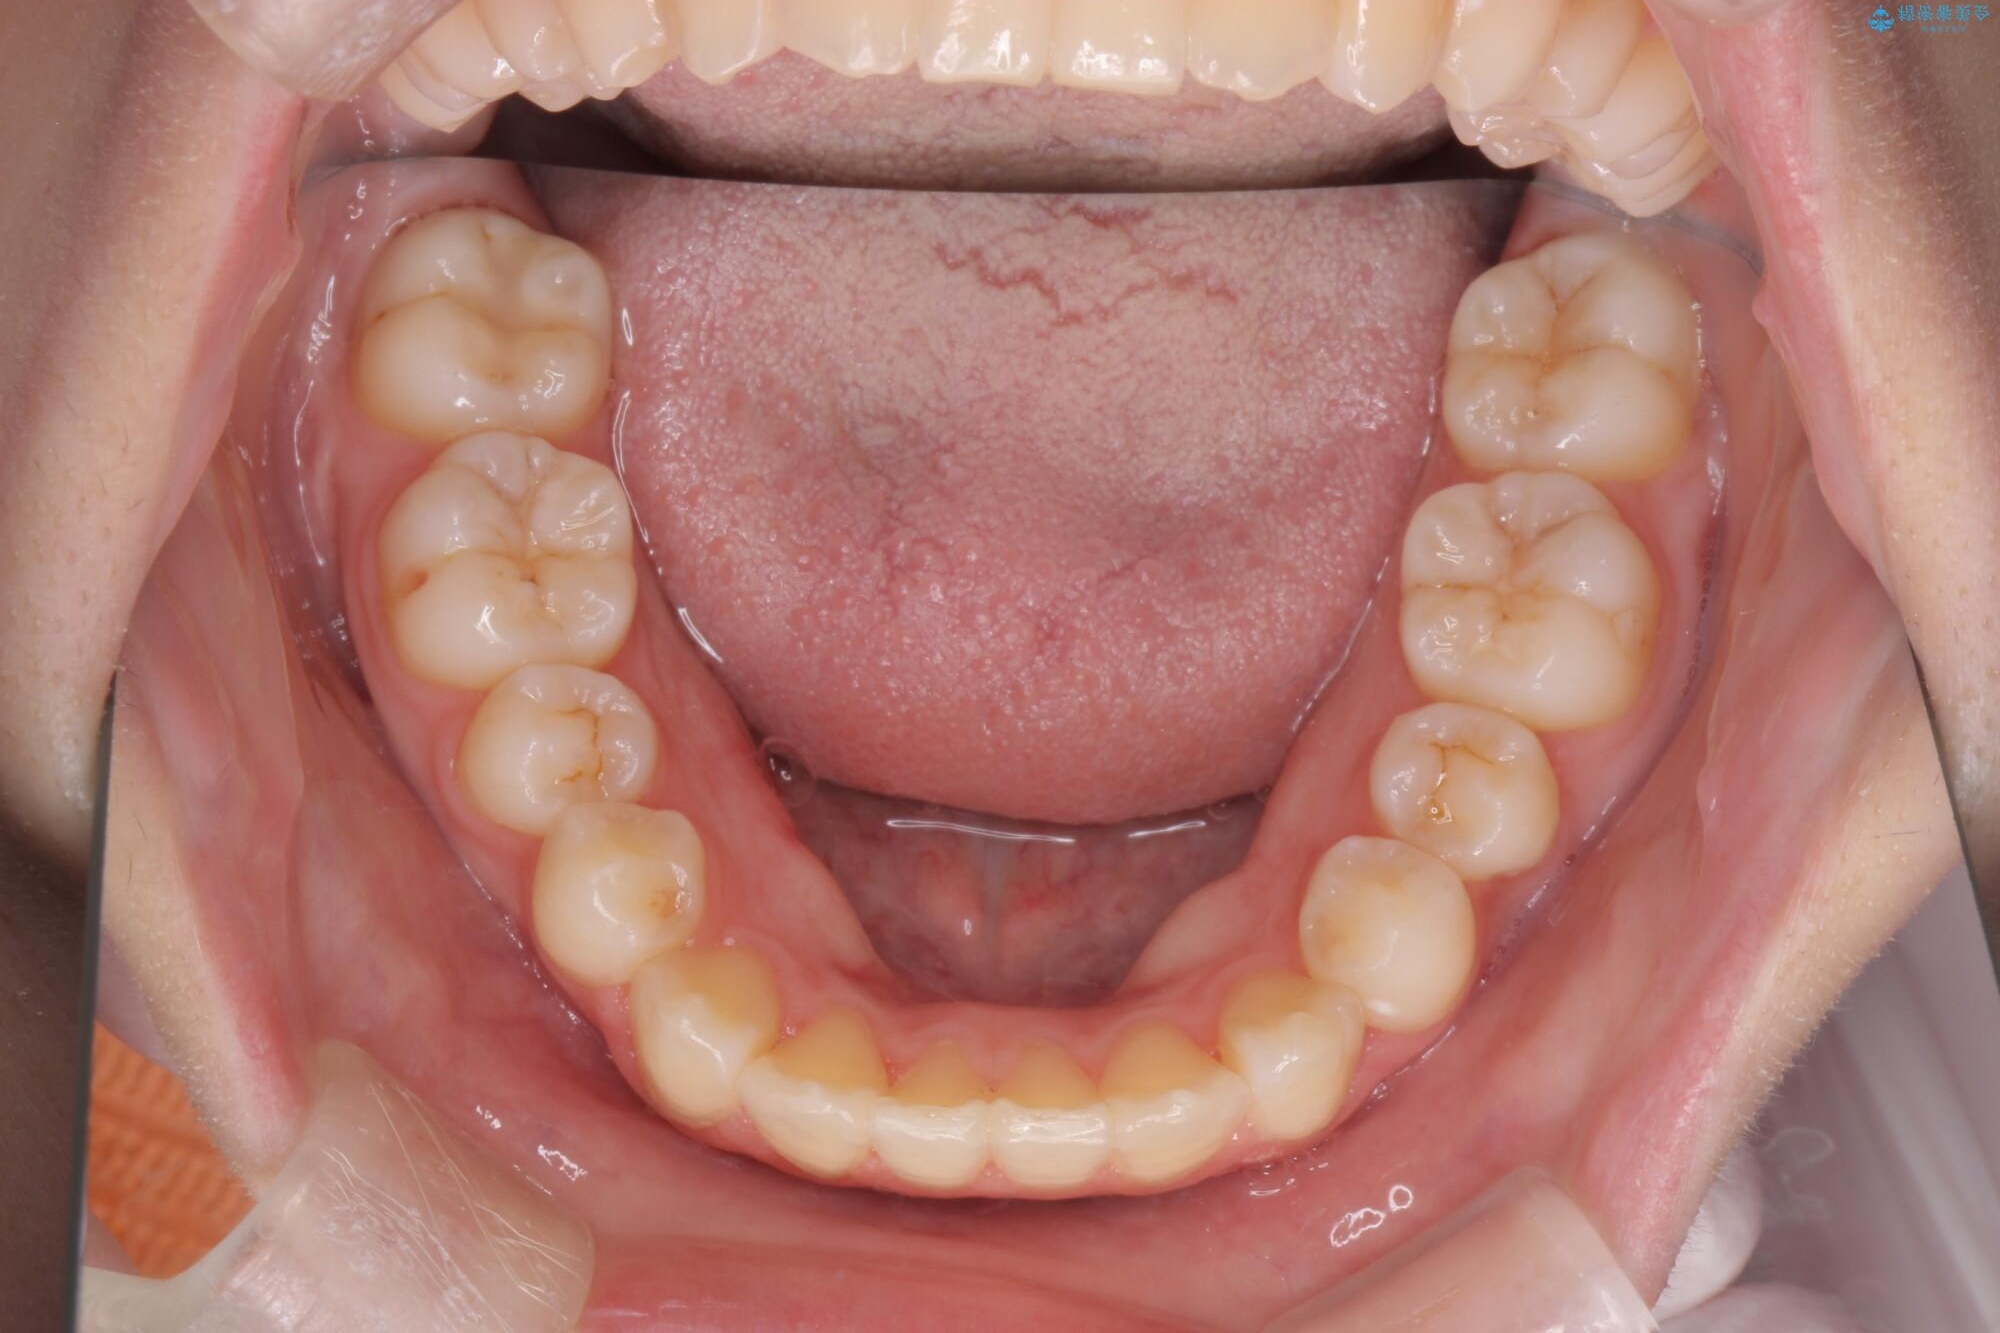

治療後

奥歯のガタつきをマウスピース矯正で改善 治療後画像 奥歯のガタつきをマウスピース矯正で改善 治療後画像 奥歯のガタつきをマウスピース矯正で改善 治療後画像